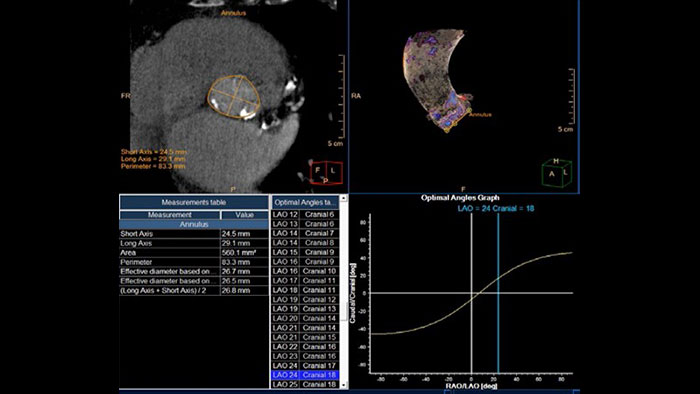

- TAVI Planning

-

CT TAVI Planning

CT imaging in TAVI to advance patient care

Provides 2D and 3D visualization and automated measurements designed to assist in proper TAVI-device sizing, on contrast-enhanced, prospectively ECG-gated axial or retrospectively gated helical CT images.

Benefits

- Area and diameter calculations for the aortic annulus, LVOT, sinotubular junction, sinus of valsalva and ascending aorta planes, as well as distance to coronary ostia from the annulus plane.

- Tools such as inspection of minimal diameter, calcifications and vessel tortuosity, to assess the peripheral vessels along the access route.

- 3D segmentation and visualization of aortic valve calcifications.